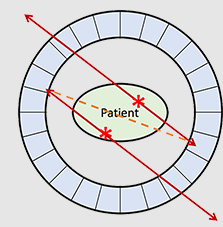

What is the relationship between each detector pair inside the ring of detectors in a PET camera?

Each detector works together with the detector opposite to it – allows it to pick up on a line of response

What is a line of response?

When the photons from an annihilation reaction are emitted, they will travel in opposite directions of one another – makes a 180-degree line almost

How does a ‘dot’ from our image translate from the reaction at the PET detectors?

The detectors create a dot on our scanned image from the point at which the 2 photons are overlapping – or where they cross each other in the ring of detectors but we still need more information to specifically determine it!

What is needed in order for the PET detectors to determine where an annihilation reaction occurred on a line of response?

Requires multiple line of responses to figure out where the intersection of where the annihilation reaction took place